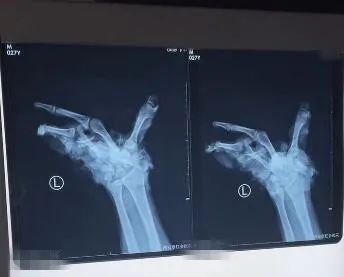

2月5日傍晚,一位来自陕西安康的27岁男子被家人紧急送到西安市红会医院。受伤男子的家属表示,当天下午,这名男子在家放炮仗时,不慎将左手炸伤。

据了解,事发当时,这名男子左手拿了两个“雷子”,本想着点燃一个扔一个,没想到用打火机点燃第一个的时候,不小心引燃了第二个,虽然第一个扔了出去,但第二个却在手中炸开......

接诊后,医生发现患者出血严重,左手腕部以及手部软组织和骨质毁损缺损,肌腱及骨质断端外露,污染严重,需要紧急进行手术。

西安红会医院手外科二病区主治医生:“患者手部伤情严重,没有再植条件。”

目前,受伤男子已进行了截肢手术,还在进一步调节中。